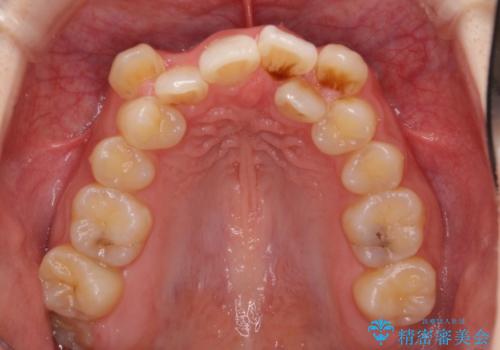

- 上下の八重歯や乱杭歯を気にして来院され患者様です。

スペースを確保するため、上下左右の第一小臼歯を抜歯し、ワイヤー装置に矯正することとしました。

結婚式の予定があったため、まずは前歯をきれいに整えるようにしました。